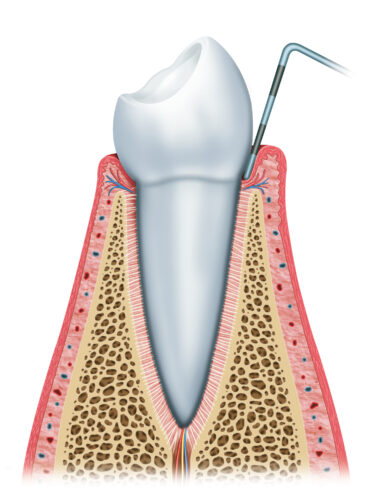

牙齦炎是牙周病前的症狀,臨床上會有牙齦紅腫、刷牙時容易流血的情形,偶爾也會伴隨著口臭。此階段的發炎尚未侵入齒槽骨內造成破壞,經過洗牙去除牙結石,並維持正確的口腔清潔習慣,即可恢復牙齦健康。